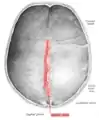

Vue interne de la suture sagittale.